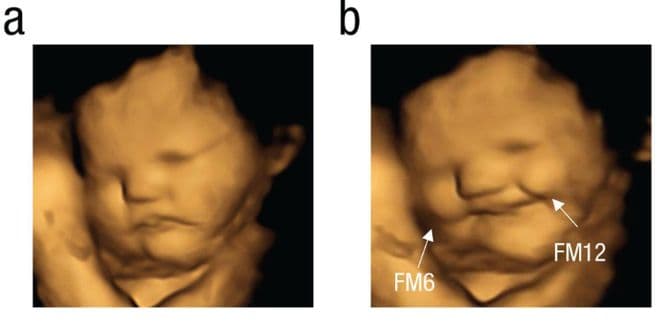

他们利用 4D 超声技术,捕获到胎儿的实时表情,严谨地证明了:原来我们自打在娘胎里就不想吃苦!!!

这张图片里可以明显看到,左边的胎儿愁眉苦脸、右边的却在眉开眼笑。是因为右边胎儿的母亲吃的是甜甜的胡萝卜粉,而左边吃到的是苦苦的羽衣甘蓝。